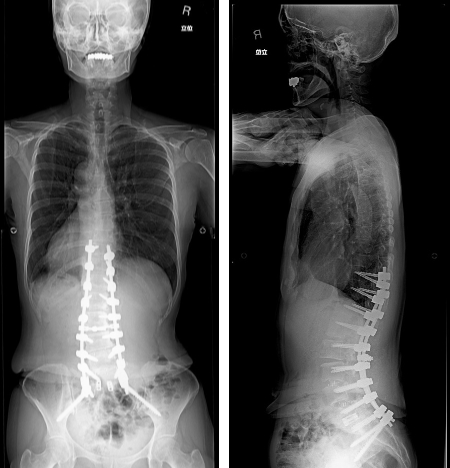

手術後脊椎全長X線写真正面像/側面像